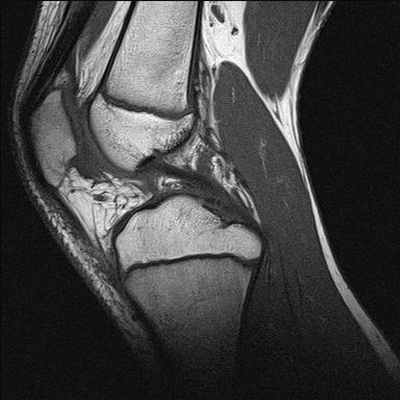

На снимке – разрыв крестообразной связки и мениска вследствие травмы колена

Для диагностики важна еще и форма мениска. В норме он в определенной плоскости имеет форму бабочки. Любые отклонения могут указывать на возможный разрыв.

Методика МРТ может выявить самые ранние изменения различных структур сустава. Например, она незаменима при оценке состояния менисков. Степени их изменения на МРТ:

- 0 степень – нормальное состояние мениска;

- I степень – в теле мениска есть очаговый сигнал усиленной интенсивности, который еще не доходит до края мениска;

- II степень – появление в мениске линейного сигнала усиленной интенсивности, не доходящего до его краев;

- III степень – сигнал усиленной интенсивности достигает крайней части мениска.

О разрыве мениска говорят только изменения III степени.